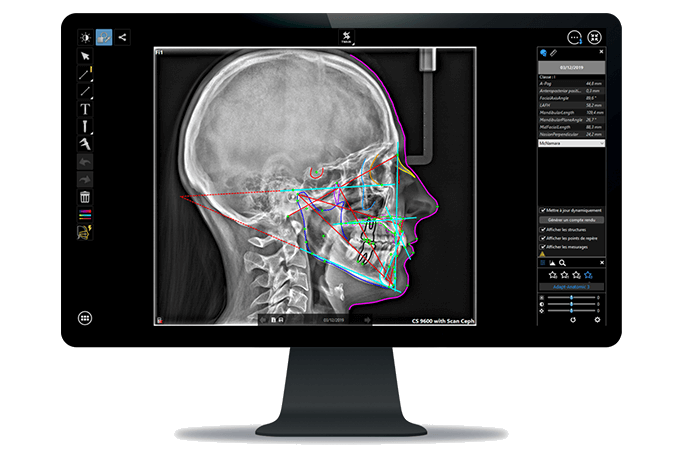

Imágenes y trazados cefalométricos en segundos

El sistema CS 8100SC 3D te aporta la capacidad de realizar exámenes cefalométricos de alta calidad en un instante. Explora imágenes en tan solo 3 segundos* para reducir el riesgo de desenfoque por movimiento y obtener trazados totalmente automáticos en tan solo 10 segundos.